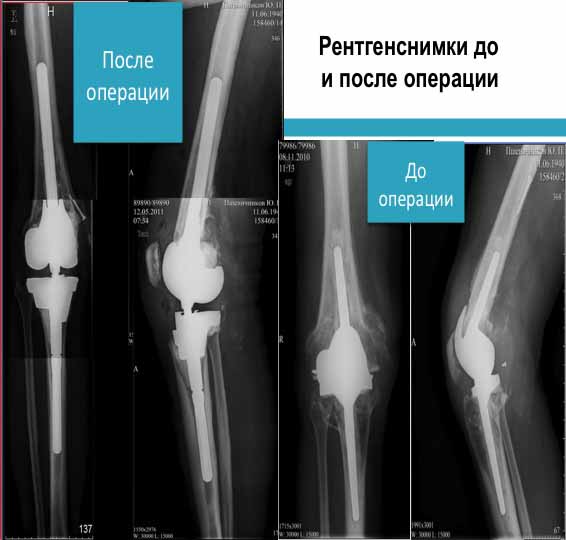

Здравствуйте! Конечно, информации для  определения типа необходимого  эндопротеза (связанный или не  связанный) мало. Но могу  посоветовать выбрать  системы ревизионного эндопротезирования  фирмы zimmer  (LCCK или Хинч с интрамедуллярными ножками) со структурными  костьзамещающими аугментами из  трабекуллярного  металла. Имеются    разные по  форме и размерам структурные аугменты,  которые "прессфит"  могут быть фиксированы  в проксимальном метаэпифизе тибиальной кости.

У нас есть опыт протезирования пациента с массивными костными дефектами бедренной и тибиальной кости. С  помощью данных аугментов обошлись без  аллокости.